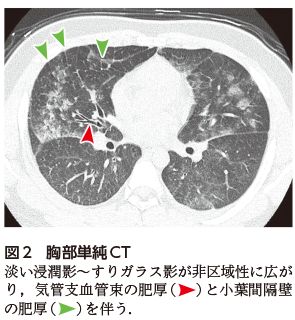

胸部単純X線写真(図1)では両側中下肺野優位にやや淡い浸潤影が広範囲にみられ,心陰影や横隔膜など既存の構造物のシルエットが不鮮明になっている.Hilar hazeを認める(図1)ことから気管支血管束や小葉間隔壁といったいわゆる広義間質にも病変があることが示唆され,肺水腫や好酸球性肺炎が鑑別にあがる.右肋横隔膜角が不鮮明であり若干の胸水を伴う可能性がある.胸部CT画像(図2)でも非区域性の淡い浸潤影とともに気管支血管束や小葉間隔壁の肥厚が確認できた(図2).心拡大や身体所見で浮腫がないことから心不全は否定的であり,3週間前の喫煙開始エピソードと合わせて急性好酸球性肺炎(acute eosinophilic pneumonia:AEP)を第一に考えた.確定診断のために気管支鏡検査を施行し,右中葉で気管支肺胞洗浄(Bronchoalveolar lavage:BAL)を行った.気管支肺胞洗浄液(BALF)の有核細胞分画では好酸球が63%を占めていた.これらより喫煙開始に伴うAEPと診断し,プレドニゾロン0.75 mg/kg/日として60 mg/日で治療を開始した.6日後に撮像した胸部単純X線写真では多発浸潤影はほぼ消退していた(図3).プレドニゾロンを4週間程度かけて漸減終了した.

• A1:両側にびまん性に浸潤影~すりガラス影を認める. 下肺野優位である.